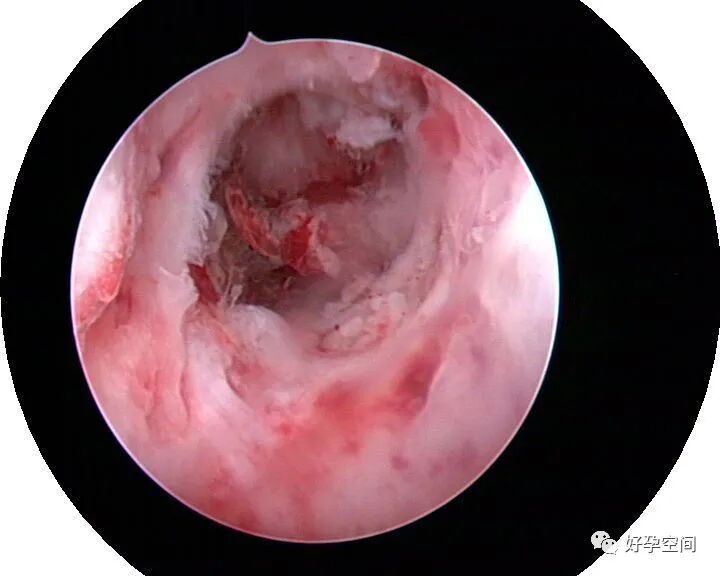

病例13:豆渣样干酪样坏死组织